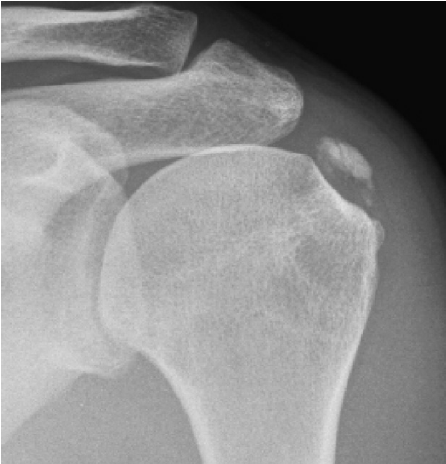

Punkcija ramenskega kalcinata

Kalcinirajoči tendinitis ramena je stanje, pri katerem pride zaradi kalcinatov v tetivi do vnetja v ramenskem sklepu. Kristali kalcija se nalagajo v slabo prekrvljenem delu tetiv in povzročajo vnetje v ramenu, ki se kaže kot vnetje ovojnice ali kot vnetje subakromialnega mešička. Bolniki opisujejo močno bolečino in omejeno gibljivost v ramenu.

Poleg kliničnega pregleda je potrebna RTG diagnostika in UZ preiskava ramena, v določenih primerih tudi preiskava z magnetno resonanco. Običajno se vnetje zdravi s počitkom, analgetično terapijo, fizikalno terapijo. V določenih primerih svetujemo tudi terapijo z udarnimi valovi (ESWT).

V kolikor so kalcinati večji od 8mm in so enakomerne strukture lahko pod ultrazvočno kontrolo opravimo tudi punkcijo kalcinata in kalcinat izperemo. Poseg se opravi v lokalni anesteziji in traja približno 30 minut. Bolečina lahko traja tudi nekaj dni po posegu. V teh primerih svetujemo jemanje analgetikov. Nekaj dni po posegu priporočamo postopno stopnjevanje aktivnosti, izvajanje vaj, plavanja, nordijske hoje in fizikalne terapije in po 2 -3 mesecih vrnitev željenim aktivnostim.